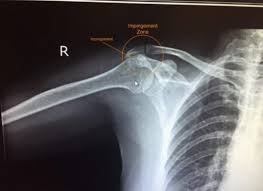

오십견은 유착성 관절낭염이나 동결견(frozen shoulder)라는 다른 이름으로 명명되어 지는데 임상적으로 볼 때 운동제한을 동반한 어깨 통증과 야간통증이 있을 때 의심하게 되는 질병으로 운동범위 검사와 어깨 MRI를 통해서 진단한다고 한다.

통증은 외전, 외회전, 신전시킬 때 악화되며 삼각근 부착부와 위팔의 바깥쪽으로 통증이 전해지기도 한다고 한다.